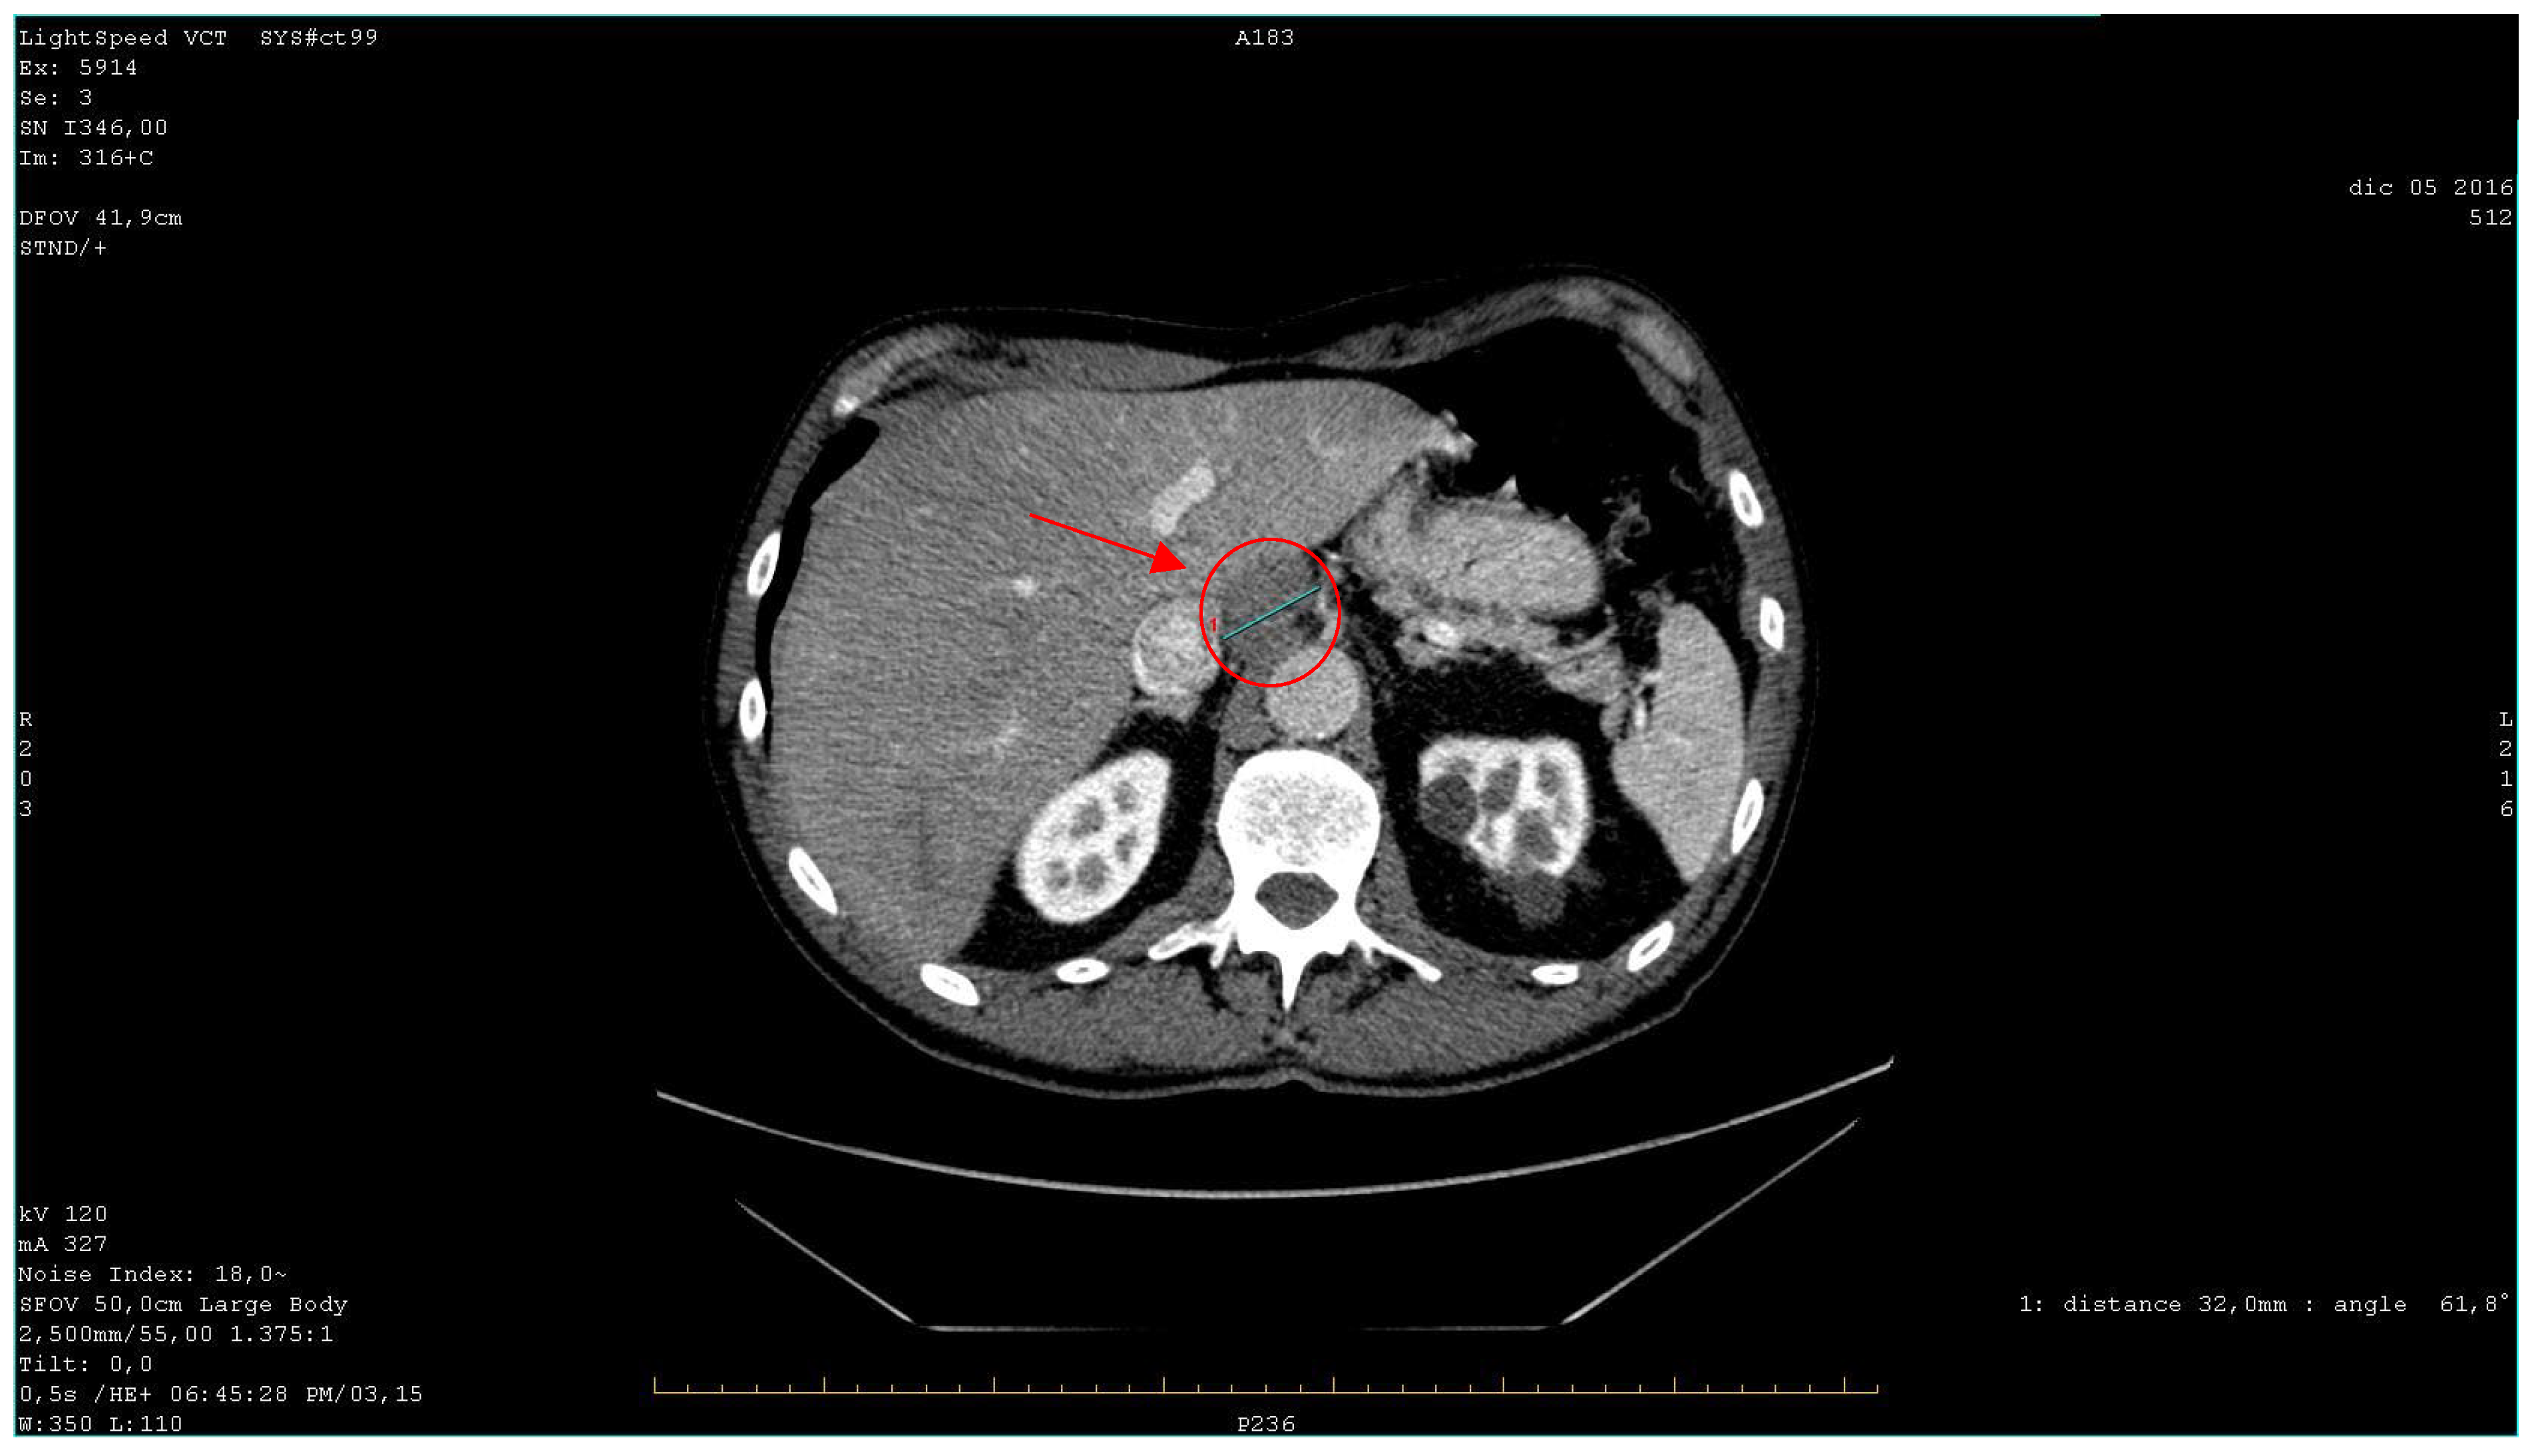

| 2016 | Patient presentation Diagnosis Abdominal ultrasound Total body CT scan | Worsening non-productive night cough, no dyspnea. Metastatic lung cancer. Presence of malignant lymph nodes near the hepatic hilum. Solid nodular- like expansive process in the right upper lobe of the lung and multiple lymphadenopathies in the mediastinum and abdomen. |